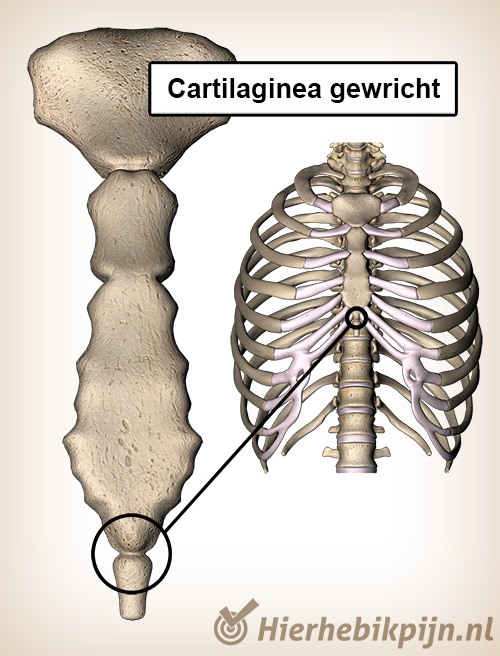

page_id_30_lead

page_id_30_body